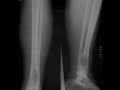

Nonossifying Fibroma

This is a 16 year old male who presented to the emergency room after twisting his ankle. Radiographs of the ankle were obtained and demonstrate a well-circumscribed lucent lesion eccentrically located within the distal metaphysis of the tibia. The lesion has a sclerotic margin with a narrow zone of transition and no internal matrix. There is no periosteal reaction, cortical destruction, or a soft tissue component. The lytic appearance, eccentric metaphyseal location, absence of internal matrix, and sclerotic margin in a patient of this age is diagnostic of a nonossifying fibroma. These are completely benign lesions without risk of malignant transformation. When the lesions meet the above described criteria, no biopsy is recommended. Over time, these lesions spontaneously heal and become sclerotic.